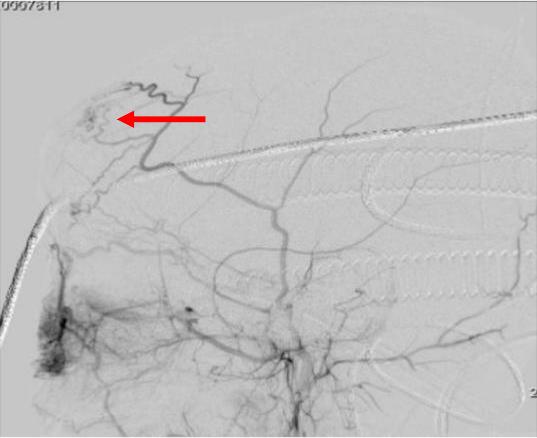

图2 患儿临床资料 A.超声引导下经皮穿刺瘤巢造影 B.术后造影显示瘤巢内畸形血管团基本消失(红色箭头指示)

完善相关术前检查后,手术历时2小时顺利完成,按小儿普外手术团队术前备选方案,超声准确定位穿刺点,超声透视引导下经皮穿刺到达瘤巢,造影证实为瘤巢位置后(图2A),在超声实时监视下注入无水乙醇,将瘤巢栓塞(图2B)破坏。术中未置入弹簧圈,避免金属异物永久存留,最大限度的节约患者医疗费用。手术创面仅有两个针眼,将病人创伤降到最低,术中出血仅2ml。术后再次造影发现瘤巢明显缩小,术后患儿无特殊不适,术后左额部包块明显缩小,包块波动消失(图2B)。